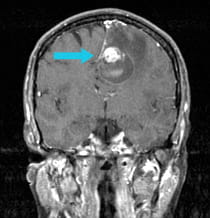

A 52-year-old woman with known breast cancer came to the hospital with progressive right-sided body weakness and a complete inability to speak. An MRI scan showed a metastatic tumor in the deep frontal region with a large amount of edema (swelling and reaction of the surrounding brain).

Pre-surgical scan shows metastasis on the frontal lobe. Post-surgical scan shows the successful removal of tumor.

Pre-surgical scan shows metastasis on the frontal lobe.